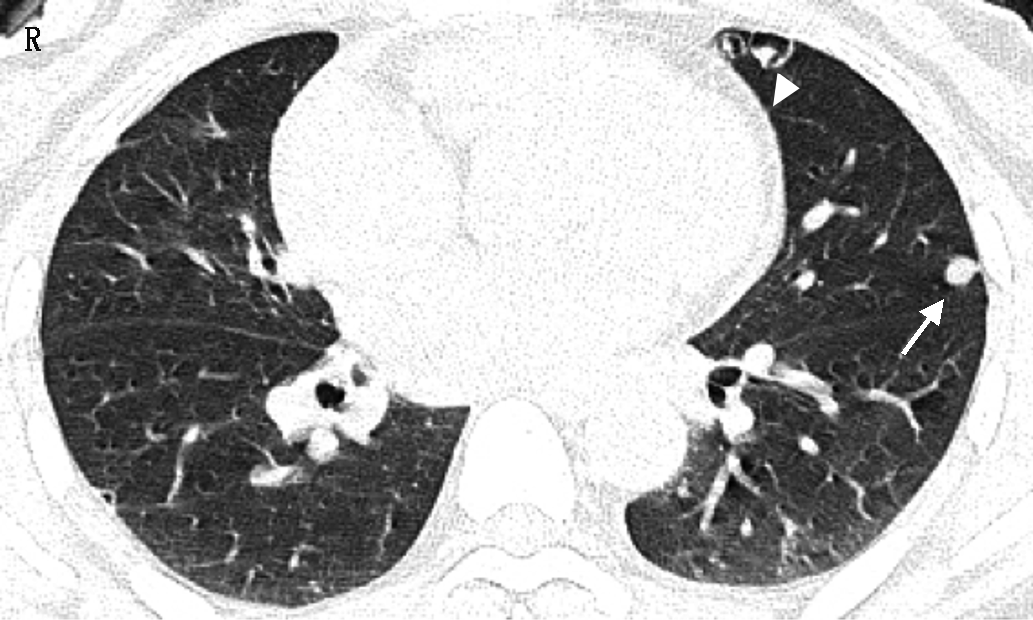

超声示:子宫增大,子宫体壁可见数个低回声团块,其中一个大小约4.6 cm×4.1 cm,左附件区见一个低回声团块,大小约5.1 cm×2.2 cm×5.9 cm。胸部CT平扫表现两肺多发大小不等结节,部分表现为实性结节(如图1、4A、图4E白箭示),部分呈囊腔样结节,壁不规则伴壁结节(如图1、4A、图4C白箭头示),部分结节内见点状钙化。病灶分布以肺外周近胸膜下为主,呈圆形或类圆形,边缘光滑,无分叶、毛刺、血管集束、胸膜牵拉等恶性征象,疑似转移。